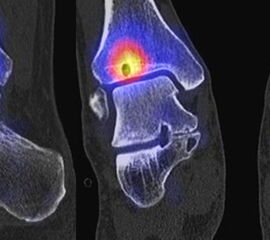

Abbildung 2.1.

Bildbeispiele symptomatische OCL

Zum Lesen der Bildbeschreibung und zur Vollansicht bitte das Bild anklicken. Bild: H. C. Rischke